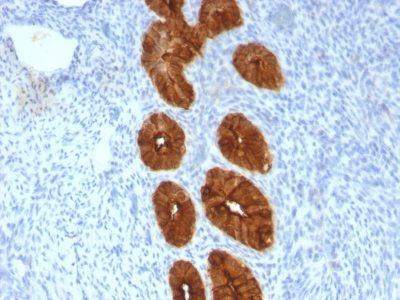

MCF-7 or MDA-231 cells. Breast, colon, ovarian, endometrial carcinoma.

Immunohistology formalin-paraffin 0.25-0.5 ug/mL|Staining of formalin-fixed tissues requires boiling tissue sections in 10 mM citrate buffer, pH 6.0, for 10-20 min followed by cooling at RT for 20 minutes|Flow Cytometry 0.5-1 ug/million cells/0.1 mL|Immunofluorescence 1-2 ug/mL|Optimal dilution for a specific application should be determined by user